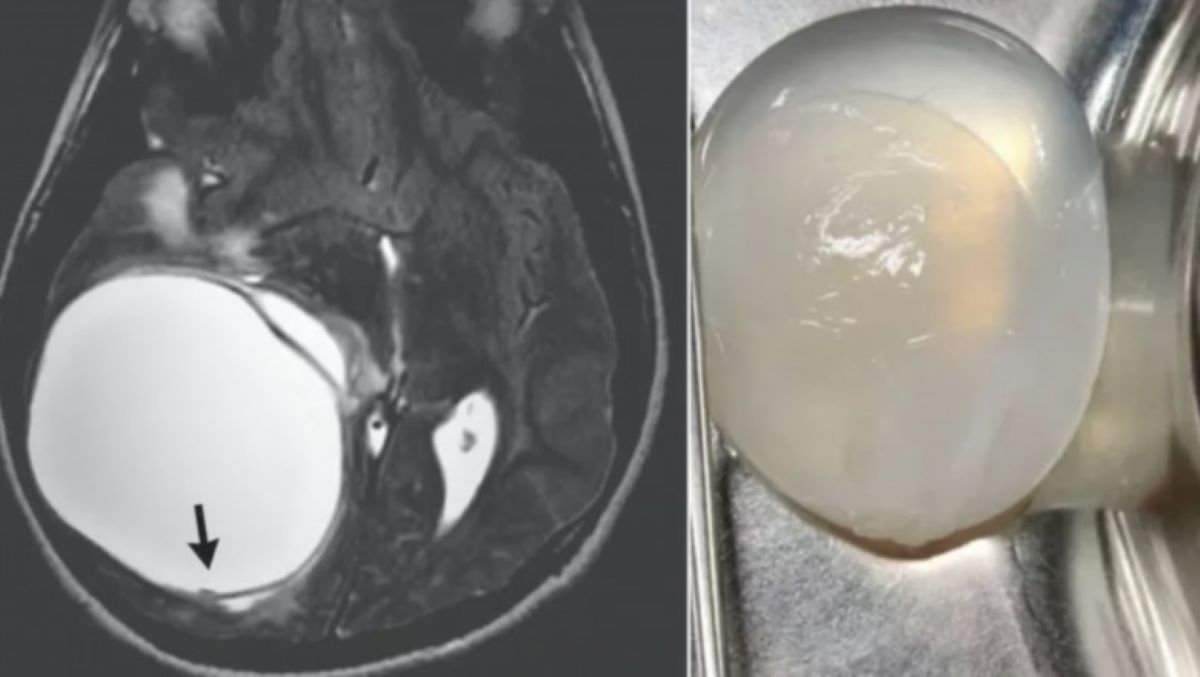

Tumoră cerebrală din cauza unor viermi intestinali. Un adolescent e 14 ani a a suferit o intervenție chirurgicală pentru înlăturarea unei tumori uriașe din creier după ce băiatul s-a infectat cu viermi paraziți, informează Newsweek.

Băiatul din India s-a infectat cu forma larvală a speciei de vierme parazit Echinococcus granulosus, care provoacă o formă a bolii echinococoză chistică. Boala se manifestă prin dezvoltarea de chisturi – pungi anormale pline cu lichid – cel mai des în ficat și plămâni. Aceste chisturi se pot forma uneori și în oase, rinichi, splină, mușchi și sistemul nervos central.

Uneori, o parte din larvele viermilor paraziți intră în sânge și ajung în alte părți ale corpului, precum în creier. Odată ajunși la destinație, paraziții declanșează formarea unui chist sau a mai multor chisturi care se lărgesc treptat.

Printre simptome se numără convulsiile, durerile de cap, vărsăturile, stările de slăbiciune și deficiențele senzoriale – acestea apar tot mai des pe măsură ce chistul se mărește și pune presiune pe creier.

„Uneori, dacă chistul se rupe, în mod spontan ori în timpul operației, lichidul din chist ar putea ieși afară, rezultând într-o reacție alergică ce ar putea provoca moartea pacientului”, a spus Thakar.